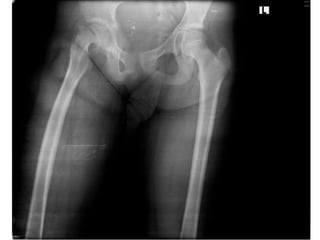

Investigation

•Film pelvis AP

•Film both hips AP

Diagnosis

• Slipped Capital Femoral Epiphysis Right Hip

Diagnosis • Slipped CapitalFemoral Epiphysis Right Hip